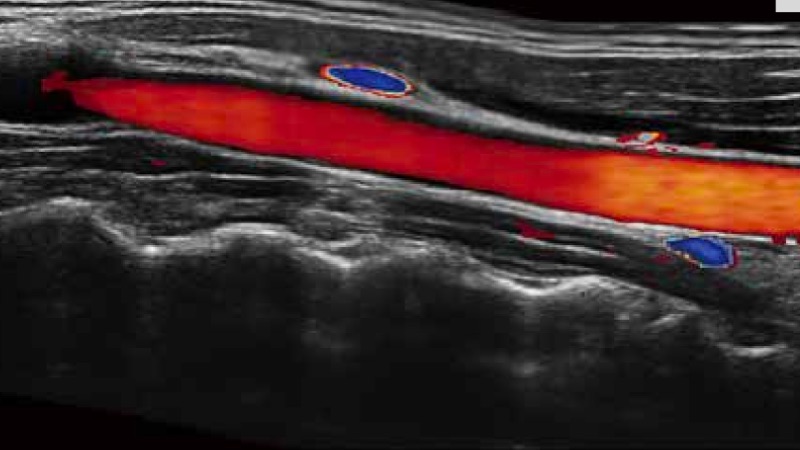

SR Flow高分辨率血流成像

高分辨率血流成像技术提高了对低速血流信号的检测能力。在提高空间分辨率的同时,也克服了血流外溢现象,为用户提供更加真实的血流动力学信息。